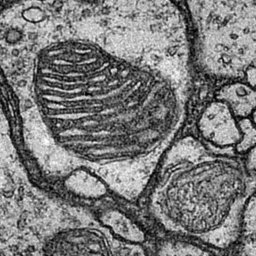

4.2.2 Drosophila Cell Image

Drosophila cell image [6] consists of 20 images including 4 classes of cell membrane, cytoplasm, mitochondria, and synapses with an image size of 1024×1024102410241024\times 1024 pixels. In experiment, we divided the images into 12 training images, 3 validation images, and 5 test images, and divided the original image size into 16 regions of 256×256256256256\times 256 pixels without overlap. The final number of images was 192 for training, 48 for validation, and 60 for evaluation. The batch size is set to 4 for training. In the segmentation images, red indicates cell membrane, black indicates cell membrane, green indicates mitochondria, and blue indicates synapses.

Figure 6: Segmentation results on Drosophila dataset

4.3.2 Results on Drosophila Cell Images

As shown in Table 3, the proposed method improved the accuracy compared to the conventional methods in many classes. In particular, our proposed AML-Net and Top-Down PDA-Module improved the accuracy of synapses, which is the most difficult class. Top-Down PDA-Module is a top-down attention mechanism using ground-truth, and it is considered that the accuracy is improved due to its ability to create attention maps that explicitly strengthen particularly difficult synapses. In addition, the accuracy of ATA-Module was improved in many classes compared to conventional methods. From the feature maps obtained from the discriminator, it can be concluded that the ATA-Module contributes to the accuracy improvement because the similarity between pixels is appropriately enhanced by the ATA-Module. Therefore, AML-Net with the appropriate combination of Top-Down PDA-Module and ATA-Module can improve the accuracy of IoU for many classes. Deeplabv3+ with ResNet-50 as its backbone does not train well on Drosophila cell images, indicating that even successful models for scene segmentation are not effective for cell image segmentation. In addition, AML-Net has better IoU accuracy than FastFCN using ResNet-50.

The top image group in Figure 6 shows that Top-Down PDA-Module and AML-Net can accurately detect synapses that are easily over-detected by conventional methods. However, our method also caused excessive false positives for cell membrane and mitochondria on the right side. The false positives were probably caused by the fact that the input image shows something very similar to cell membrane and mitochondria. In the lower group of images, U-Net and Top-Down PDA-Module fail to detect mitochondria, and misidentify them as mitochondria in some cell membranes, while ATA-Module and AML-Net correctly identify mitochondria, reducing the number of undetected or false positives. Thus, we can see that AML-Net is able to recognize mitochondria by utilizing the advantages of both ATA-Module and Top-Down PDA-Module.